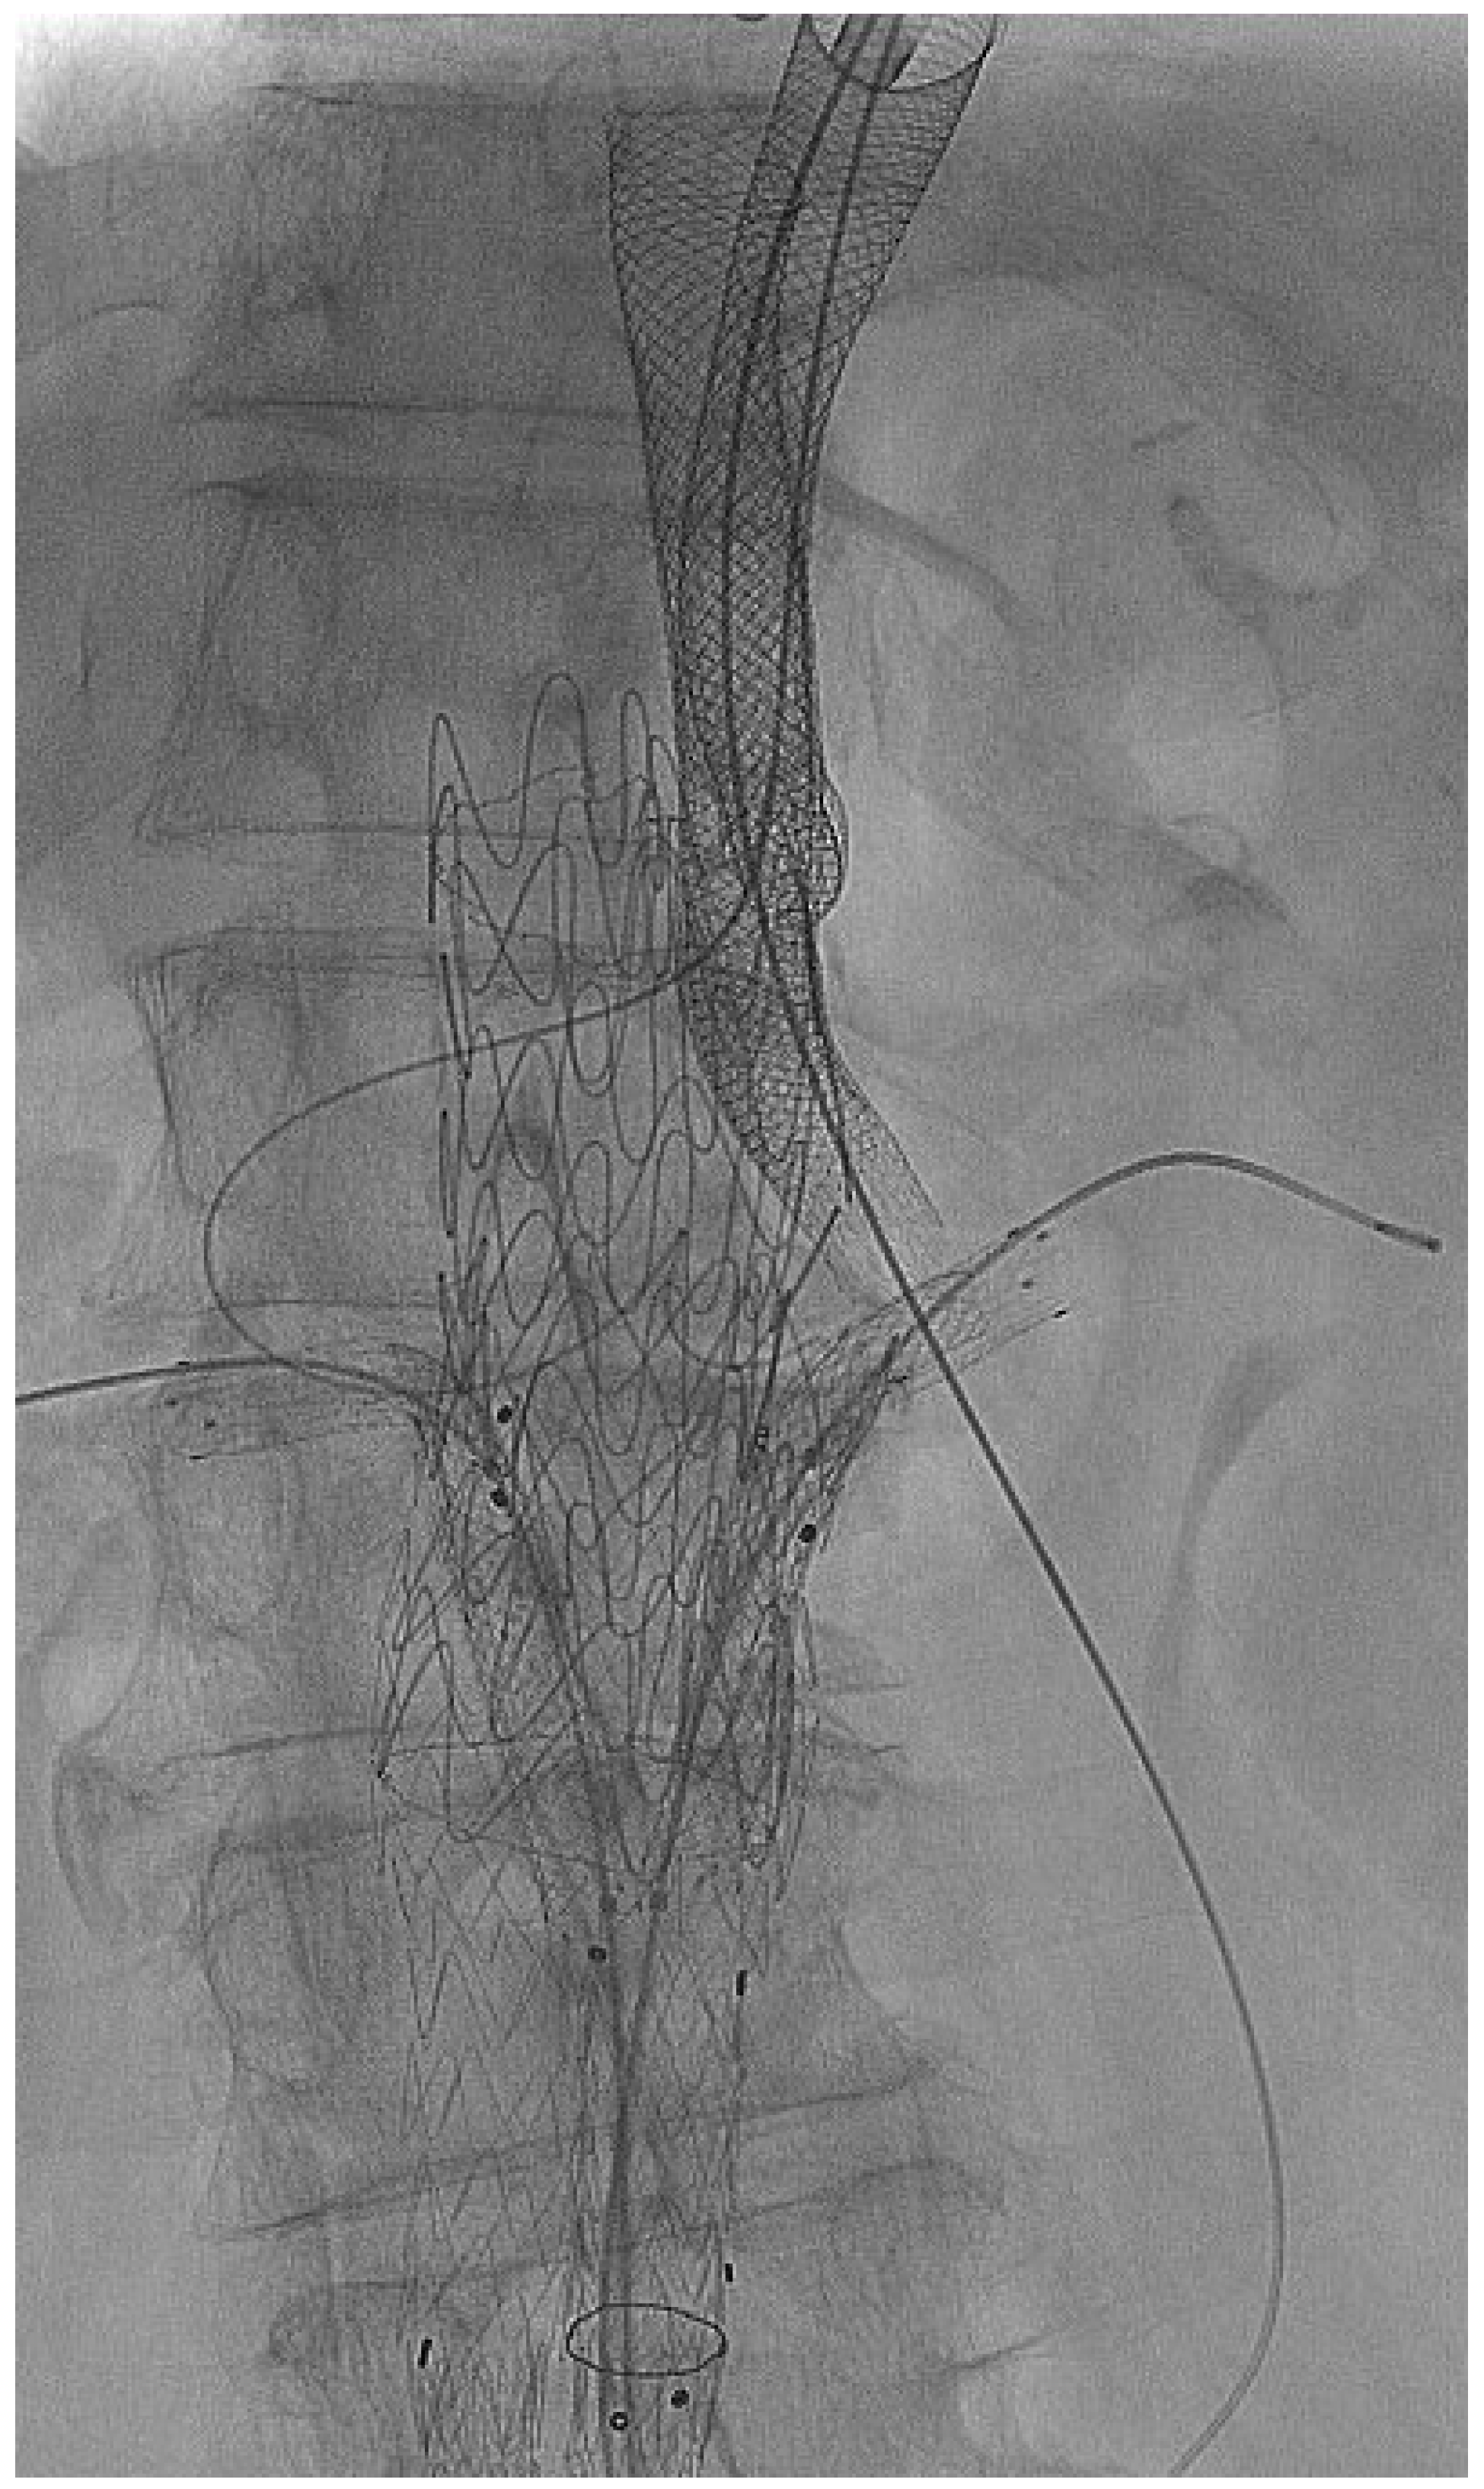

2.3. Endovascular Aortic Repair and Parallel Stent Graft Technique

| Number of parallel grafts | 39 (23 Chimneys, 16 Periscopes) | |